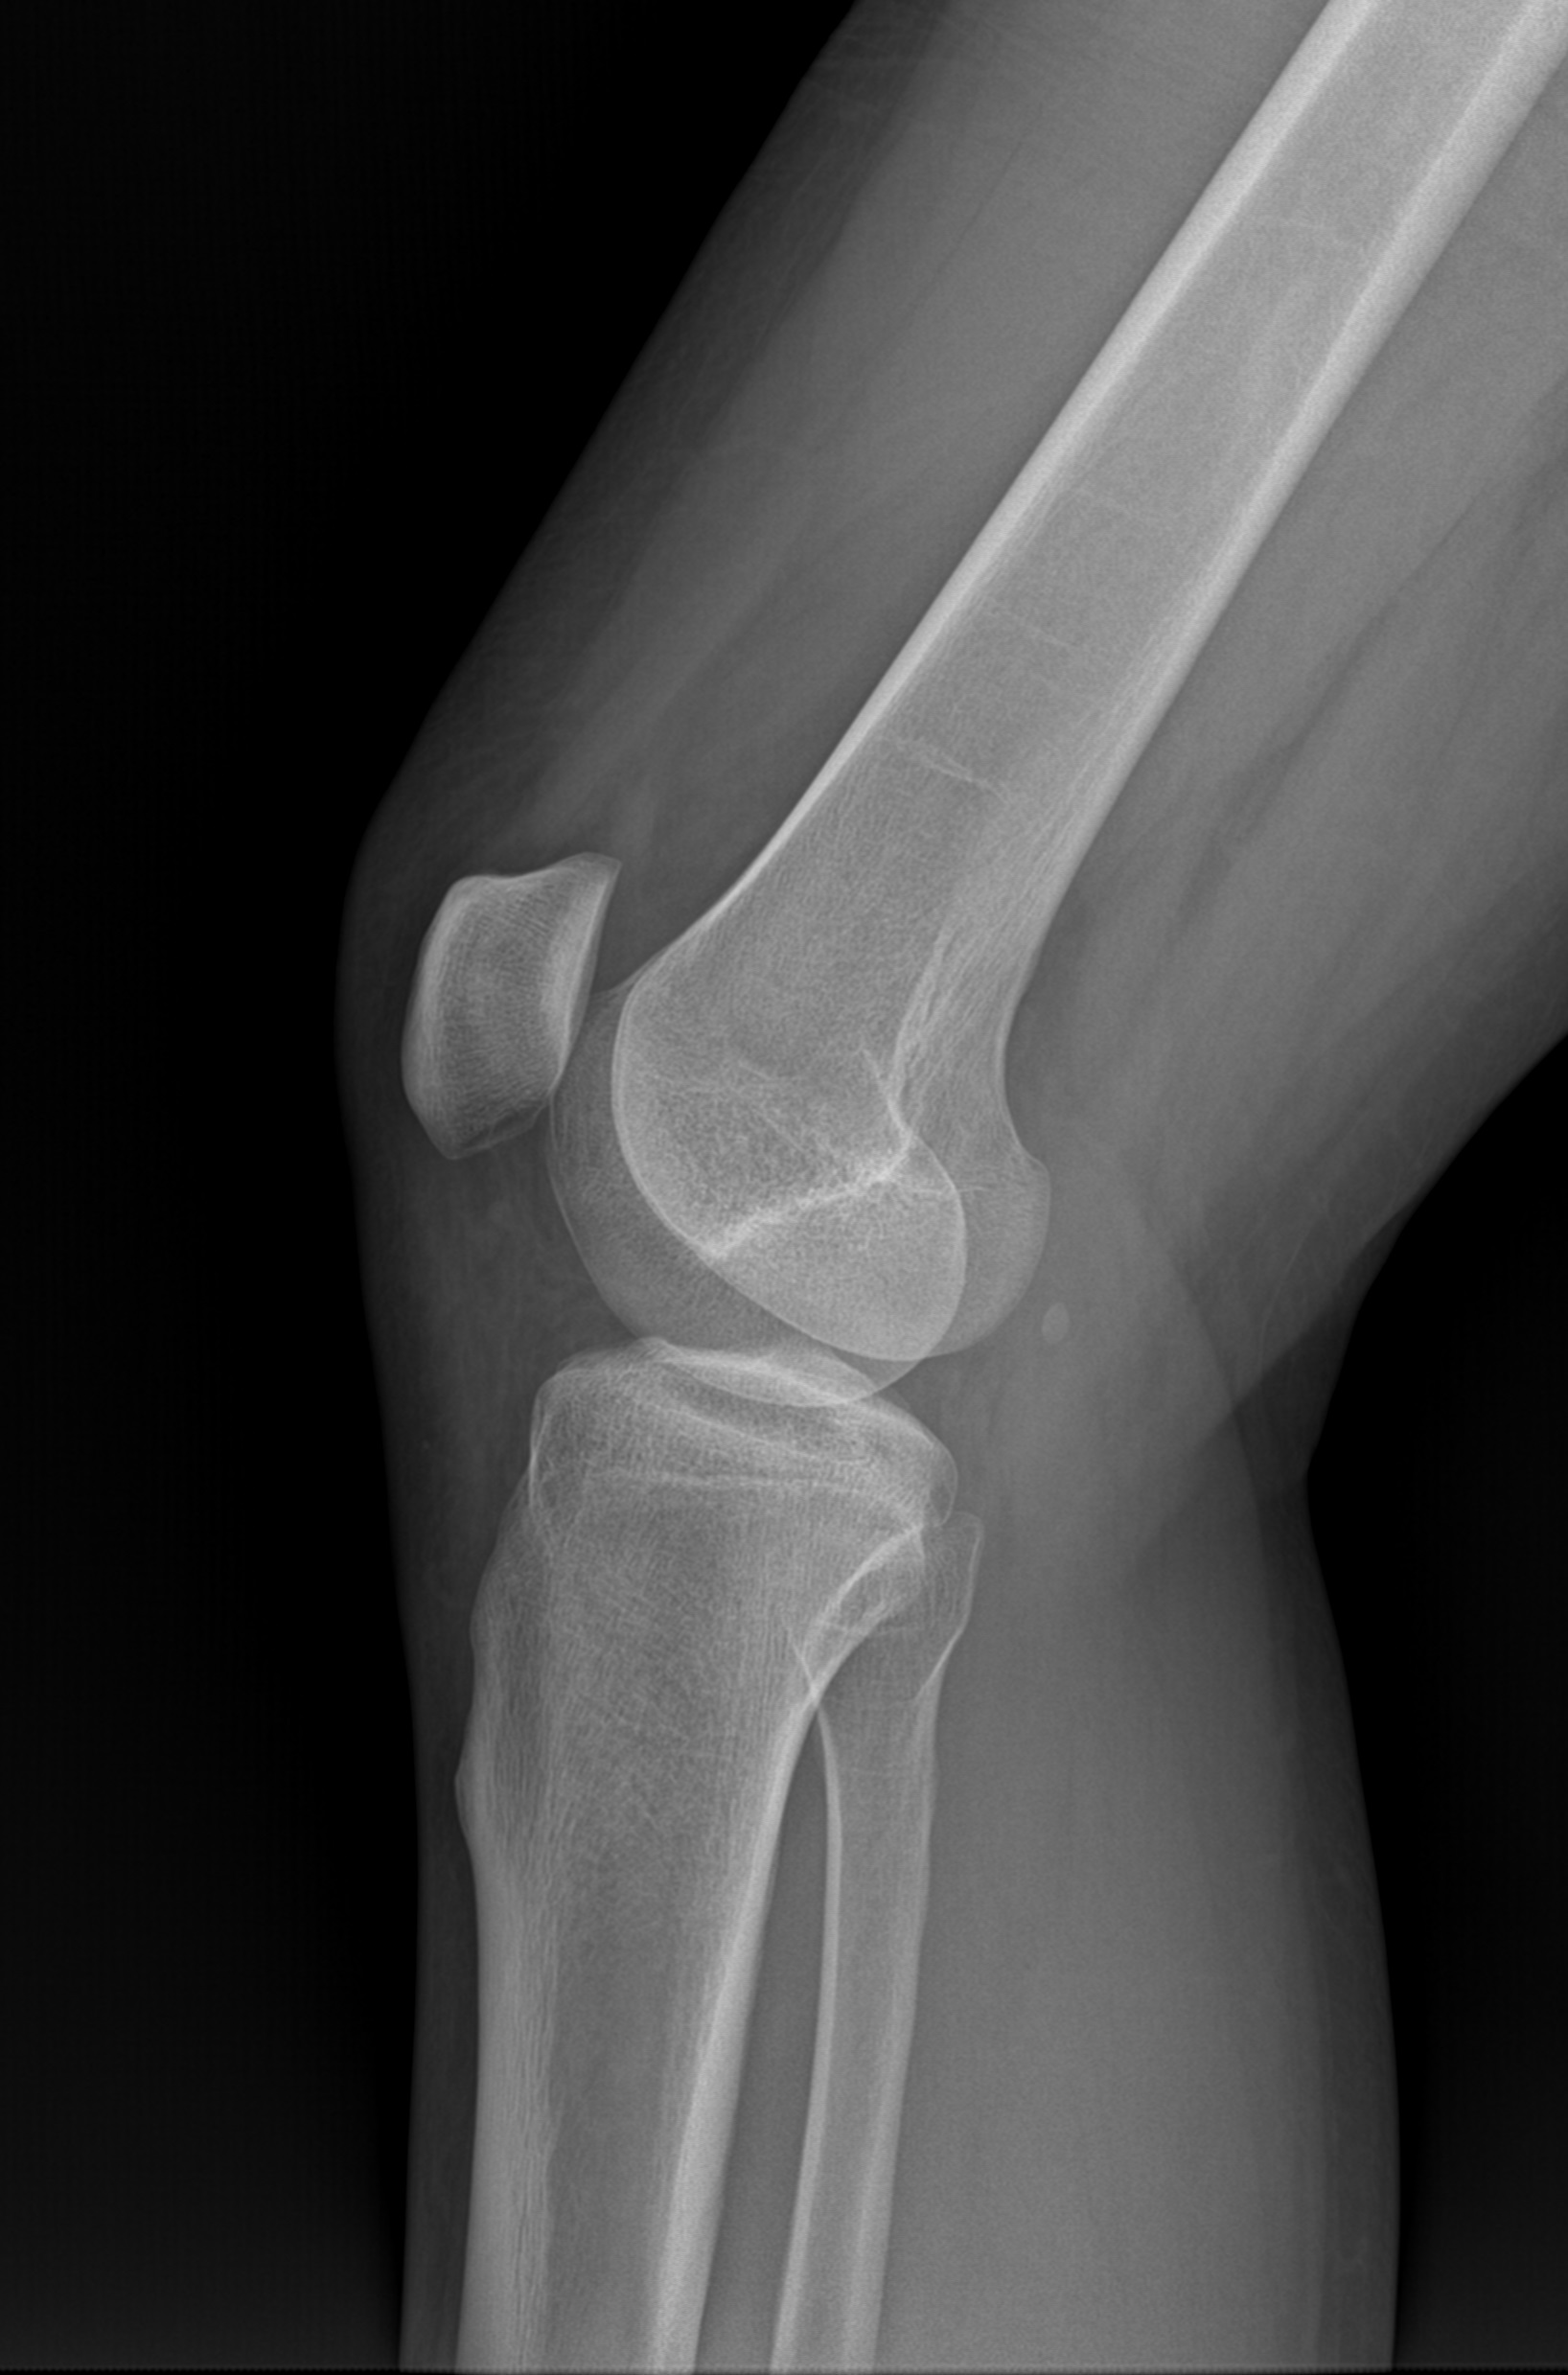

采用17x17英寸無(wú)線大平板,整板無(wú)拼接,圖像視野寬闊,成像清晰細(xì)膩。